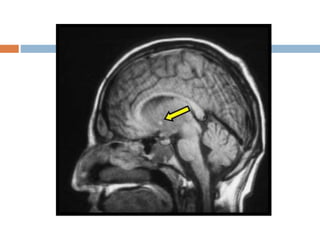

Entry slice phenomenon

 When unsaturated spins in blood first enter in to

a slice or slices.

 Characterized by bright signal in a blood vessel

at the first slice.

 Confused with thrombosis.

 Gradient echo flow techniques to differentiate.

 Solution

 Use spatial saturation bands before the first and

after the last.

Entry slice phenomenon When unsaturated spins in blood first enter in to a slice or slices.  Characterized by bright signal in a blood vessel at the first slice.  Confused with thrombosis.  Gradient echo flow techniques to differentiate.  Solution  Use spatial saturation bands before the first and after the last.